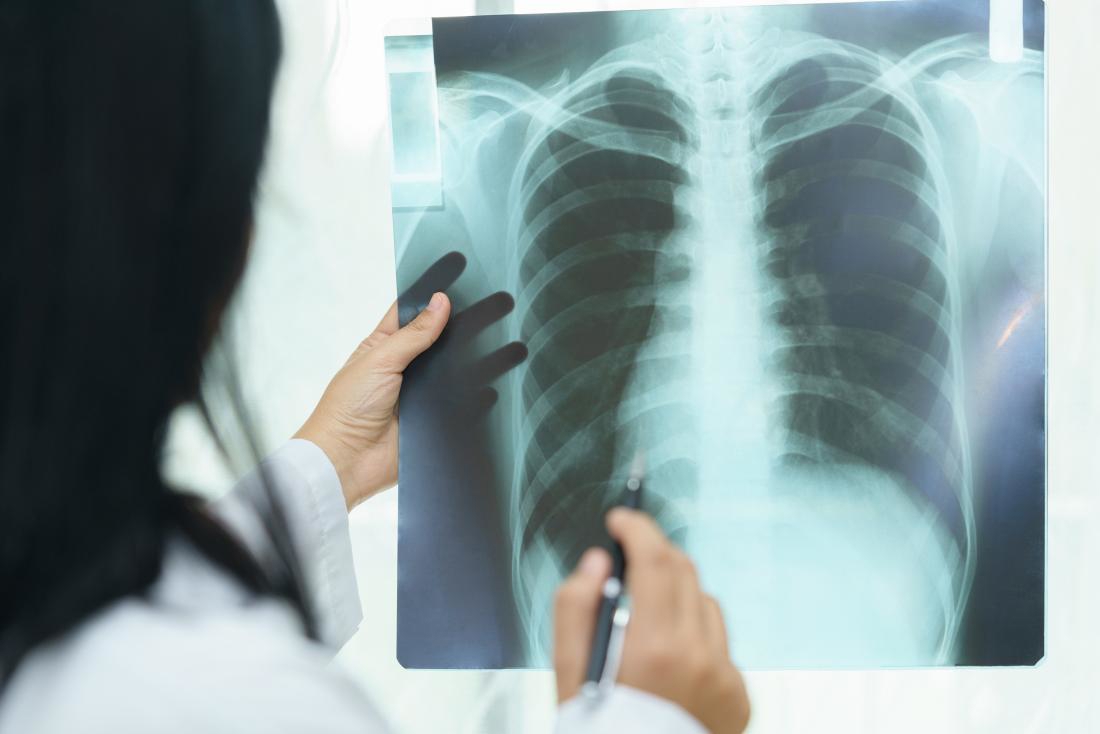

Kết quả chụp X-quang và CT ngực ghi nhận hình ảnh tràn khí khoang màng phổi phải kèm theo tổn thương nhu mô phổi (đám đông đặc ở thùy trên và phân thùy S5 phổi phải). Bác sĩ nhận định tình trạng này do chấn thương phổi trong lúc gắng sức.

Hồi tháng 4 năm nay, khi đang chơi thể thao, anh N.D.T 36 tuổi (Long Biên, Hà Nội) bỗng có triệu chứng đau ngực, khó thở, phải đến khám tại Bệnh viện Đa khoa Đức Giang. Tại đây, hình ảnh phim X-quang phổi của bệnh nhân cho thấy có dịch, có khí. Các bác sĩ chẩn đoán anh bị tràn khí màng phổi tự phát. Ngay lập tức, bệnh nhân được chỉ định dẫn lưu màng phổi cấp cứu, mổ khâu kén khí, cầm máu, làm sạch khoang màng phổi.

Bác sĩ khuyến cáo người bệnh cần nhận diện sớm triệu chứng như đau ngực đột ngột, khó thở khi gắng sức, sau đó nhanh chóng đến cơ sở y tế để được chẩn đoán, can thiệp kịp thời. Trong quá trình điều trị, chụp cắt lớp vi tính (CT scan) lồng ngực đóng vai trò quan trọng giúp chẩn đoán chính xác và đánh giá mức độ tổn thương trong các trường hợp tràn khí màng phổi.

So với phương pháp chụp X-quang ngực thông thường, với khả năng dựng hình cắt lớp theo nhiều mặt phẳng, CT scan có độ nhạy cao hơn, giúp phát hiện những lượng khí nhỏ không rõ trên phim X-quang, đồng thời cung cấp hình ảnh chi tiết về nhu mô phổi và khoang màng phổi.